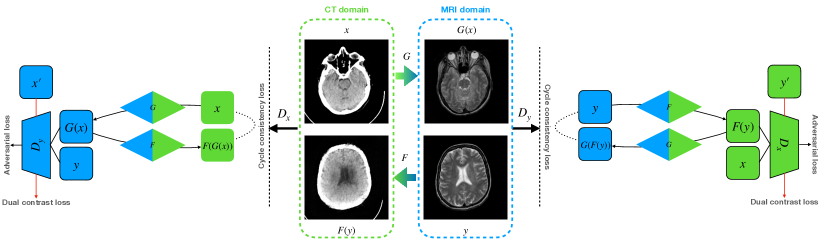

In this section, we discuss our proposed DC-cycleGAN model for medical image synthesis in detail. The aim is to learn a bidirectional mapping function between MR and CT images using unpaired data, i.e., using MR and CT images from different subjects. Assume and indicate sets of CT and MR images, respectively, where and . Similar to the cycleGAN, our DC-cycleGAN model (see Fig. 3) consists of two generators and for learning CT-to-MR and MR-to-CT mappings, respectively, where and represent synthesized MR and CT images, and two discriminators and for distinguishing real MR and CT images from the synthetic or negative ones, respectively. In another word, the discriminators aim to distinguish whether the input image belongs to class 1, i.e., real image, or class 0, i.e., synthesized image or a sample from the source domain. In addition, each discriminator includes a DC loss that leverage the advantages of samples from the source domain as negative samples to enforce the synthesized images falling far away from the source domain.

However, Directly applying cycleGAN to synthesize samples from another modality, i.e, MR-to-CT, cannot generate high-quality images as there are no direct constraints between real source and synthetic images [39]. In other words, using adversarial and cycle consistency losses cannot guide the generator to learn a robust mapping in the target domain. To address this issue, in this study, we leverage the advantage of samples from the source domain as negative samples during the training of discriminators. To achieve this, the concept of dual contrast is used, which is discussed the next subsection.

3.3 Dual contrast

The original discriminator aims to distinguish the real images in target domain from the synthesized images by the generator . Although using these images helps the generator to learn features from the domain, it can easily fool the discriminator by slightly changing some features of the samples from the source domain to the target domain, i.e., the discriminator identifies the synthesized image as a real one. Thus, the generator cannot learn a proper mapping in the target domain. To alleviate this issue, as shown in Fig. 4, we add an additional term, called dual contrast (DC), to leverage the advantage of samples from the source domain (see Fig. 4), as follows:

| (4) |

In this case, real images are considered class 1, and both synthesized images and samples from the source domain are considered class 0. Thus, the discriminator’s goal in our proposed method is to distinguish whether the input image belongs to class 1, i.e., real image, or class 0, i.e., synthesized image or a sample from the source domain. Adding images from the source domain as negative samples force the discriminator to guide the generator to synthesize image far away from the source domain in the latent space.